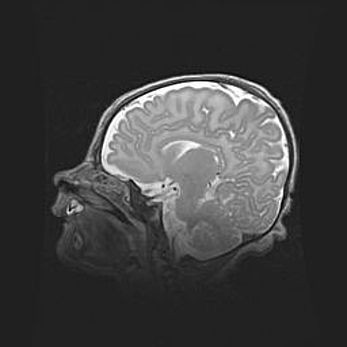

Мальформация Денди-Уокера. Киста задней черепной ямки.

Агенезия мозолистого тела.

Возраст: 2,5 месяца

Вес: 2420 г

Пол: женский

Окружность головы: 37 см

Срок гестации: 32 недели

Мальформация Денди—Уокера — редкий вид патологии ЦНС, представляющий собой врожденный порок развития каудального отдела ствола и червя мозжечка, ведущий к неполному раскрытию срединной (Мажанди) и латеральных (Лушка) апертур IV желудочка мозга. Для этогно синдрома характерна триада симптомов: гипотрофия червя мозжечка и/или полушарий мозжечка, кисты задней черепной ямки, гидроцефалия различной степени. В 70% случаев порок сочетается и с другими аномалиями головного мозга, в частности с агенезией мозолистого тела.